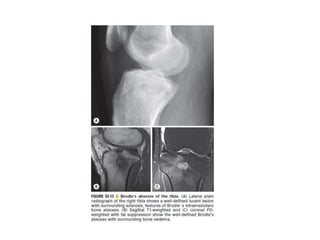

• Brodie abscess is an intraosseous abscess related to a

focus of subacute pyogenic osteomyelitis.

• They are found characteristically in subacute pyogenic

osteomyelitis, usually of staphylococcal origin, but

cultures are often negative.

• common in children, more typically boys.

• Appear mainly in the metaphysis, particularly that of the

distal or proximal portions of the tibia.

Brodie's Abscess

Plain radiograph

• lytic lesion often in an oval configuration that is

oriented along the long axis of the bone

• surrounded by a thick dense rim of reactive

sclerosis

• lucent tortuous channel extending toward growth

plate prior to physeal closure-tunneling

(pathognomonic)

• periosteal new-bone formation +/- adjacent soft-

tissue swelling

• may persist for many months

• CT

• central intramedullary hypodense cystic lesion

with thick rim ossification

• extensive thick well-circumscribed periosteal

reaction and bone sclerosis around the lesion

could be seen

• MRI

• The “penumbra sign” - a rim lining of an abscess

cavity with higher signal intensity than that of the

main abscess on T1-weighted images